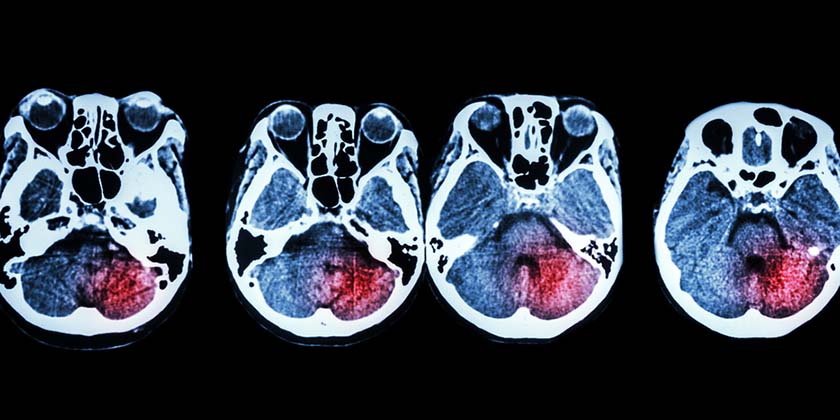

Тысячи пациентов с диагнозом «кровоизлияние в мозг» прошли лечение в больнице «Шиба». Но те, кто лечился в последние годы, выписывались в лучшем состоянии и после этого умирали на треть реже. Это заслуга системы искусственного интеллекта (ИИ) , разработанной в Израиле. Она расшифровывает компьютерную томографию головы и на основе снимков расставляет приоритеты для врачей.

Внедрение искусственного интеллекта, который расшифровывал компьютерную томографию головы в отделении неотложной помощи, способствовало снижению смертности среди пациентов на 30%. Такова ключевая цифра исследования, опубликованного в августе 2023 года в научном издании International Journal of Emergency Medicine.

Искусственный интеллект расшифровывал каждый новый снимок, отдельно выделял снимки, на которых обнаруживал повреждения, требующие неотложного вмешательства, такие как внутричерепное кровотечение, инсульт или аневризма головного мозга.